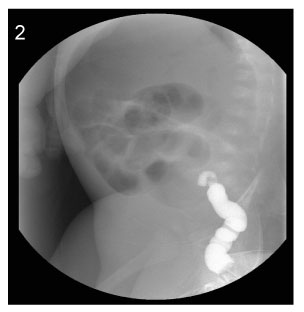

Fig. 3

Image of simple X-ray at the age of 43days (Case No. 4).

Fig. 3 Image of simple X-ray at the age of 43days (Case No. 4).